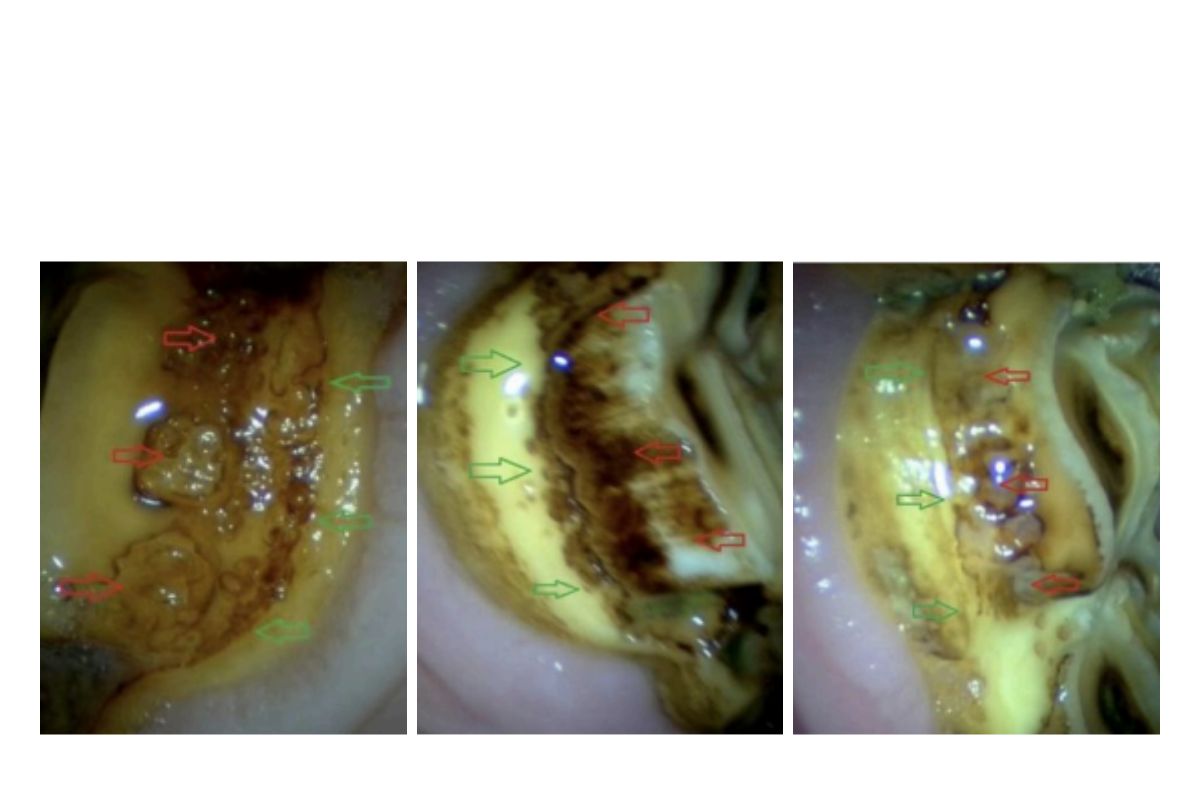

Peripheral caries of various grades depicted by red arrows, with new shelf of health cementum shown by green arrows

Peripheral caries is diagnosed by visual examination of the decay by your veterinarian. The severity is graded depending on the degree and distribution of decay, and ranges from 1.1 (minor decay of the outer cemental layer) to 4 (decay resulting in fracture of the teeth/loss of normal tooth architecture).